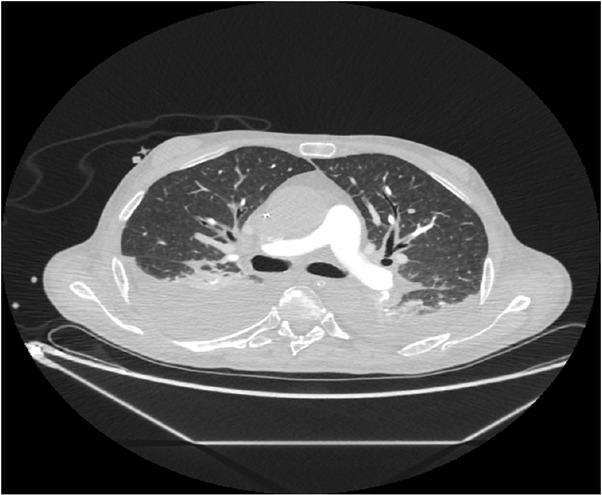

We considered the following as differential diagnoses of shock: hypovolemia, pulmonary embolism, pneumothorax, and septic shock. The postoperative PiCCO measurements and TEE ruled out hypovolemia (Table 2). Pulmonary embolism and pneumothorax were excluded through a thoracic CT-scan (Fig.5). Postoperative bacteriological screening revealed no pathogen and sepsis blood markers (PCT and presepsin) were inconclusive. Moreover, hemodynamic parameters pointed to cardiogenic shock (Table 2).

Postcontrast thoracic CT-scan revealing bilateral pleural effusions. No signs for central thromboembolism or pneumothorax were documented.

Considering the association between the hemodynamic parameters, cardiac enzyme elevation, ECG changes, ultrasound findings, and absence of coronary obstruction pointed towards the diagnosis of reverse Takotsubo cardiomyopathy was reached. Further imagistic and urinary findings excluded the presence of pheochromocytoma. Evidence-based therapy for stress cardiomyopathy was applied.